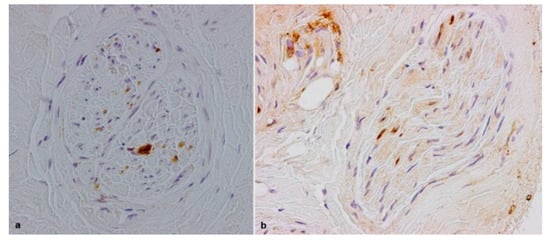

3.2. Pathological Results